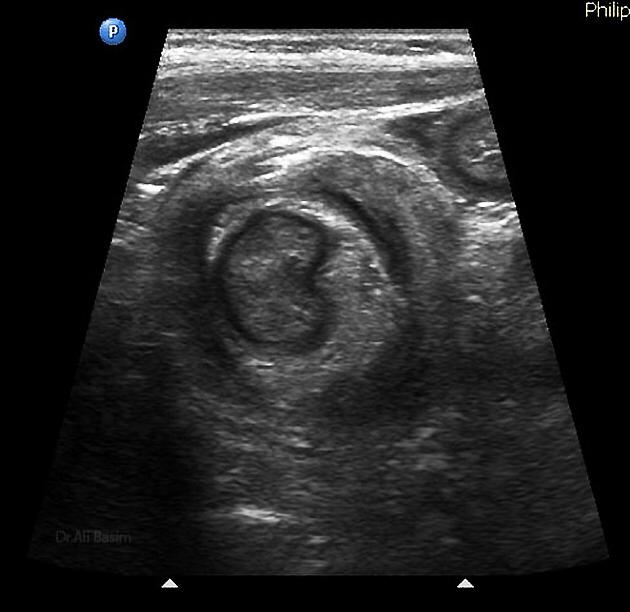

Ultrasonido de Glándula Tiroides

El término nódulo tiroideo se refiere a cualquier crecimiento anormal de las células tiroideas que forman un tumor dentro de la tiroides. Aunque la gran mayoría de los nódulos tiroideos son benignos (no cancerosos), una pequeña proporción de estos nódulos sí...